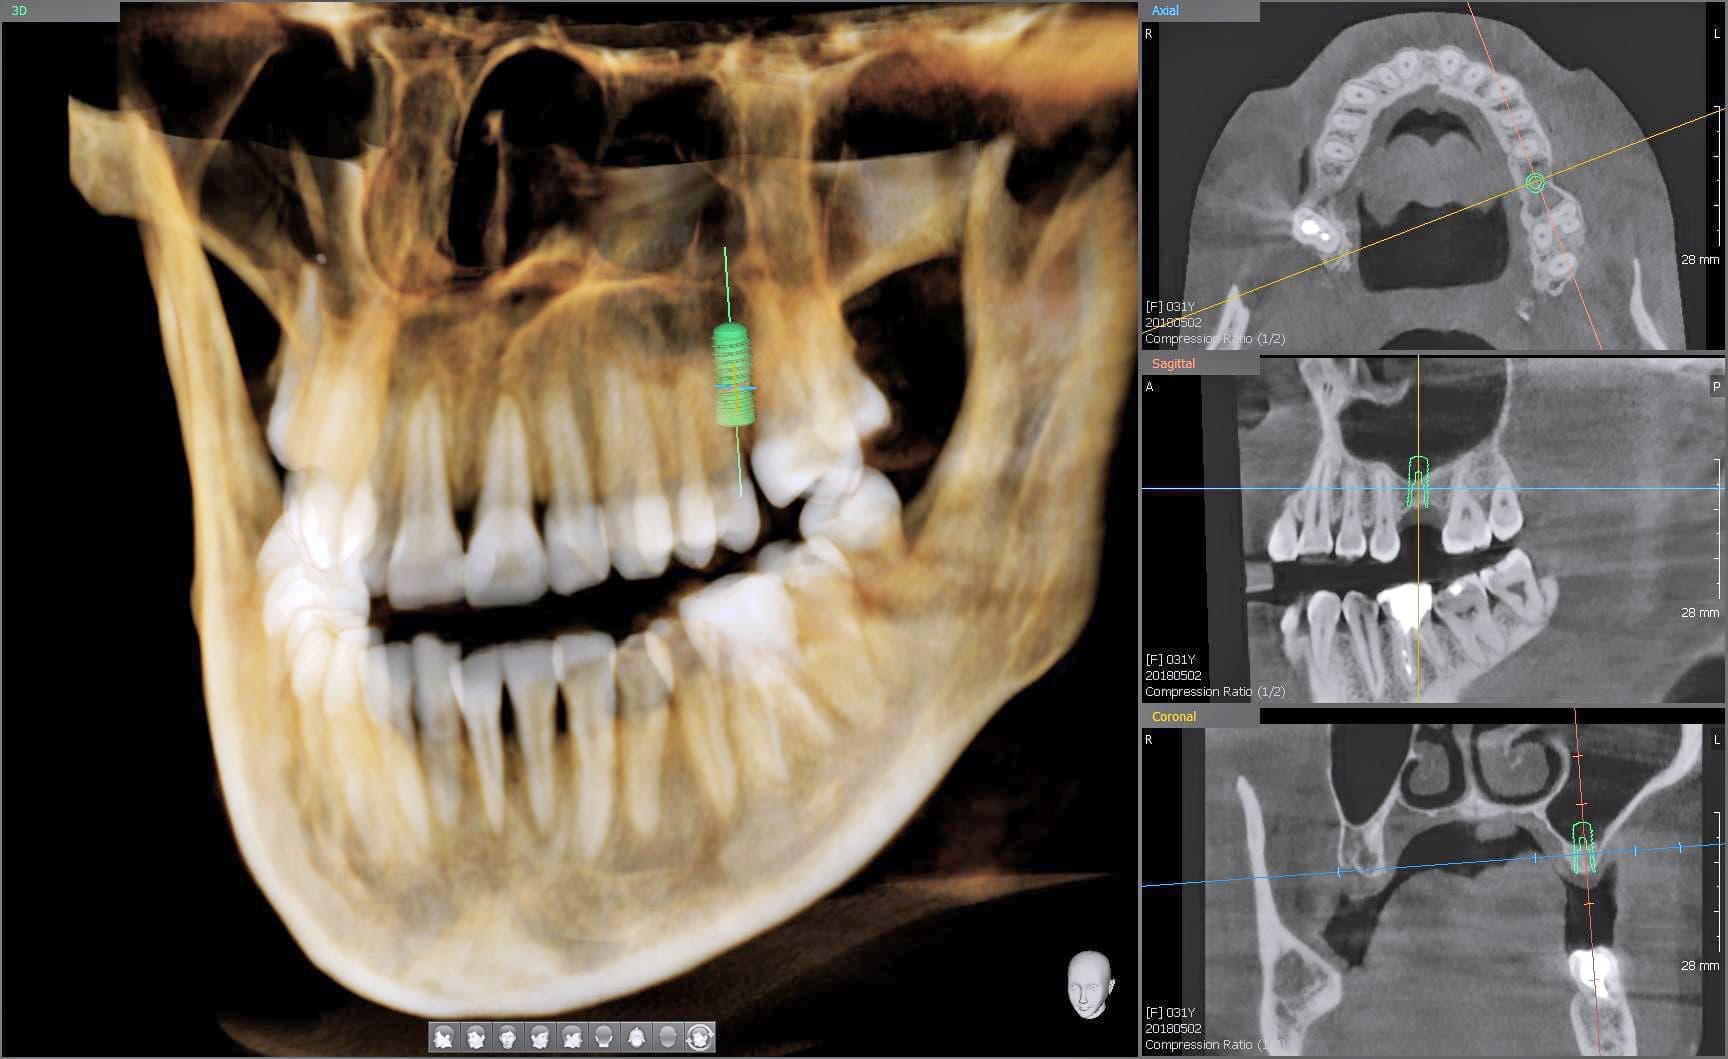

CT 3D デジタルレントゲン

PaX-i3D CT Roentgen

高精細で被爆量も少なく安心

当院では、歯科用CT3Dデジタルレントゲンを活用し、身体への負担を少なく、状況を詳しく把握し、的確な治療を提供出来るよう心掛けております。

CTデジタルレントゲンに使われているX線センサーは高感度で照射時間も短く、より低線量でのレントゲン画像の取得が可能となり、お子様にも安心です。

インプラント手術や歯周病治療、歯の根の病気に関係する治療の正確な診断、治療計画には、CTによる撮影が欠かせません。

例えば、親知らずの抜歯や骨内に埋伏している過剰歯の抜歯等、正確な位置や神経や血管等との距離を3次元的に把握することで負担の少ない安心な処置が行えます。